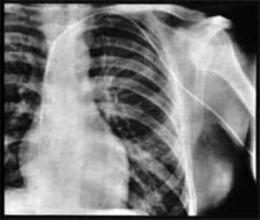

福斯曼曾提出了一个大胆的想法,将一根导管插入至心脏,通过这根管子可向心脏内注入药物或测量血压,在当时这种想法自然会被认为是疯狂的了。但为了证明这种技术的可行性,福斯曼决定在自己身上进行实验。

在对自己的前臂进行局部麻醉后,他将一根导管插入了肘前静脉,并向内推进了65cm,直到他的心脏。随后,为了证明所言不假,他带着这根管子,不顾周遭人的尖叫声,硬是来到了放射科,为这根插在他右心房内的导管照了相。不过可惜的是,在当时这种方法还是没有受到众人的认可。